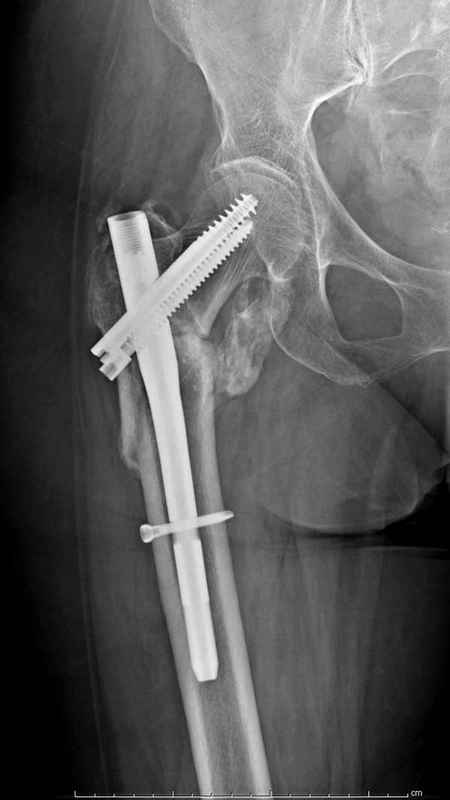

Из фиксаторов, мы бы применили цефаломедуллярные, потому что они "по закону моментов" из-за короткого рычага от центра головки к диафизу и по принципу "головка диафиз" механически лучше выдерживают нагрузки, чем пластины.

Здесь пара случаев фиксации похожих переломов:

первый высокоэнергетическая травма 36 лет

судя по картинкам с ЭОПа явно использовались приемы непрямой репозиции под его контролем, а так же интраоперационный ЭОП-контроль положения винтов, без такого контроля операция может ухудшить ситуацию (опять же учтите сроки) т.к. результат буде зависеть в большей степени от искусства хирурга, а не от технологии